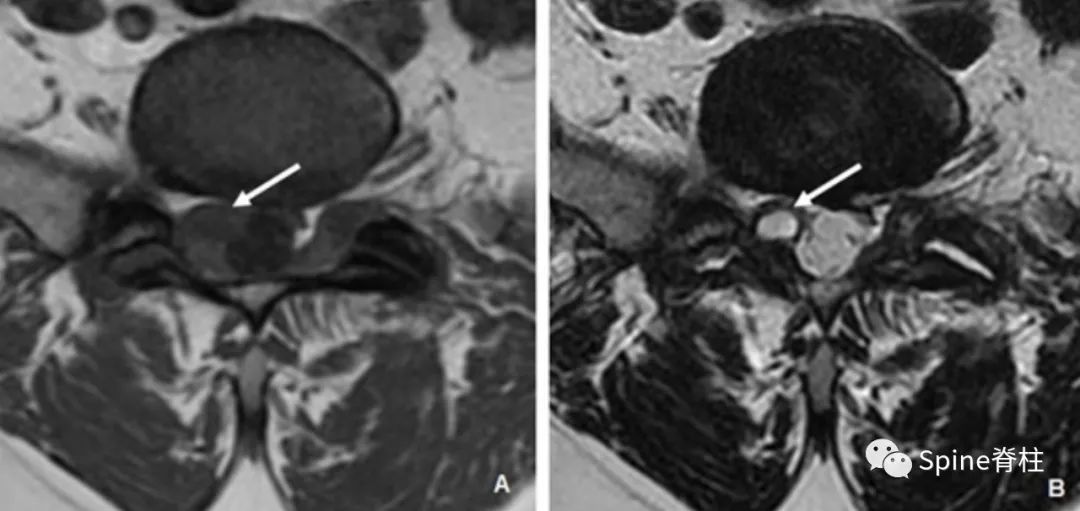

1. 滑膜囊肿 (synovial cysts):具有滑膜内皮细胞,与小关节腔连通并含有滑液。通常与相邻的小关节病变有关,且主要发生在腰段。在MRI上,滑膜囊肿边界清楚、光滑, 位于硬膜外且邻近小关节 。在T1和T2加权像上,囊肿内的蛋白质成份可显示出比周围脑脊液更明显的信号强度(下图)。囊壁可能会钙化,在T1和T2加权图像中呈现低信号,增强后囊壁可见强化。

一名55岁患者腰椎MRI提示L5/S1滑膜囊肿(箭头),右侧S1神经根明显受压。囊肿邻近肥大的小关节突

2. 假性囊肿 (pseudocysts): 假性囊肿或神经节囊肿可能是小关节、黄韧带或后纵韧带囊肿,具体取决于其解剖起源。其与真性囊肿具有共同的症状和影像学特征,但不与小关节腔直接相通。这些囊肿被认为是由脊柱活动中韧带的退变引起(下图)。

一名62岁患者腰椎MRI提示L4-L5平面的椎管内硬膜外黄韧带囊肿(蓝色箭头),绿色箭头为邻近肥厚的黄韧带